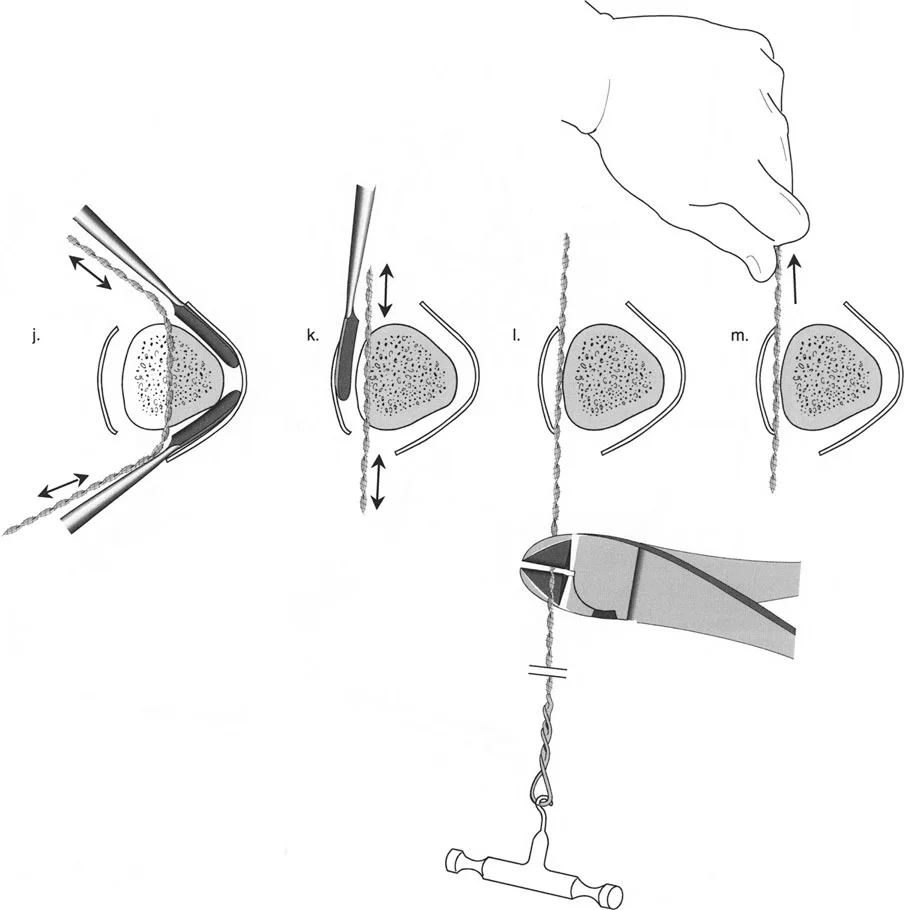

قيود الأسلاك والدبابيس في القاعدة 2

لتحقيق هذه الترجمة الضرورية والمقصودة بسلاسة باستخدام إطار دائري كامل الأسلاك، يلزم استخدام أسلاك الزيتون المعاكسة (counter-opposed olive wires). تعمل أسلاك الزيتون كقوى سحب ديناميكية، تسحب قطعة العظم على طول الحلقة أثناء فتح المفصلات. بدون أسلاك الزيتون، سيبقى العظم ثابتًا بينما تتحرك الحلقة عبر الأنسجة الرخوة، مما يسبب نخرًا شديدًا في الجلد.

على العكس من ذلك، إذا تم استخدام دبابيس نصفية (مسامير شانز)، فإنها تقيد العظم بطبيعتها بالحلقة. نظرًا لأن الدبابيس النصفية هي أذرع صلبة (مثبتة من طرف واحد بالحلقة ومغروسة في العظم من الطرف الآخر)، فإنها لا تسمح للعظم بالانزلاق على طول محور السلك. هذا يجعل أسلاك الزيتون غير ضرورية للترجمة في منشآت الدبابيس النصفية، ولكنه يتطلب من الجراح التأكد من أن الدبابيس النصفية قوية بما يكفي (عادةً دبابيس بقطر 5 مم أو 6 مم مطلية بهيدروكسي أباتيت) لتحمل لحظات الانحناء الناتجة عن الترجمة.

| تقابل الأسلاك | استخدم ما لا يقل عن سلكين زيتون متقابلين لكل قطعة إذا كنت تتجنب الدبابيس النصفية. | الأسلاك الزيتون الفردية ستسبب قصًا ودورانًا غير مرغوب فيه حول محور السلك. |